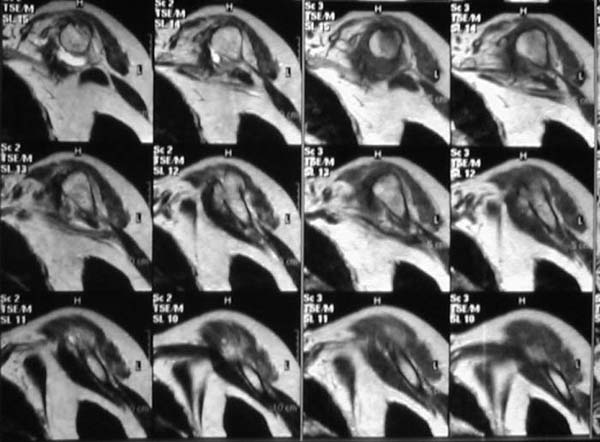

Уважаемые коллеги! Женщина, 60 лет. 3 недели назад упала с упором на отведенную левую руку. Почувствовала боль в левом плечевом суставе. За помощью не обращалась. 2 недели "мази и припарки". Затем - рентгенограмма (r1 и r2), жалобы на боли, ограничение движений...

Активное отведение 80 гр., при пальпации - головка плечевой кости безболезненно вправляется и тут же самостоятельно вывихивается. Наложена косыночная иммобилизация, рентгенография (r3) и МРТ. В нашем диагностическом центре МРТ исследование плечевого сустава выполнено впервые, опыта у нас маловато :(. Вопросы: уточнение диагноза? какие исследования провести? тактика лечения?

МРТ1 МРТ2 МРТ3 МРТ4